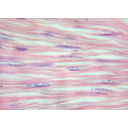

MUSCOLATURA striata.jpg